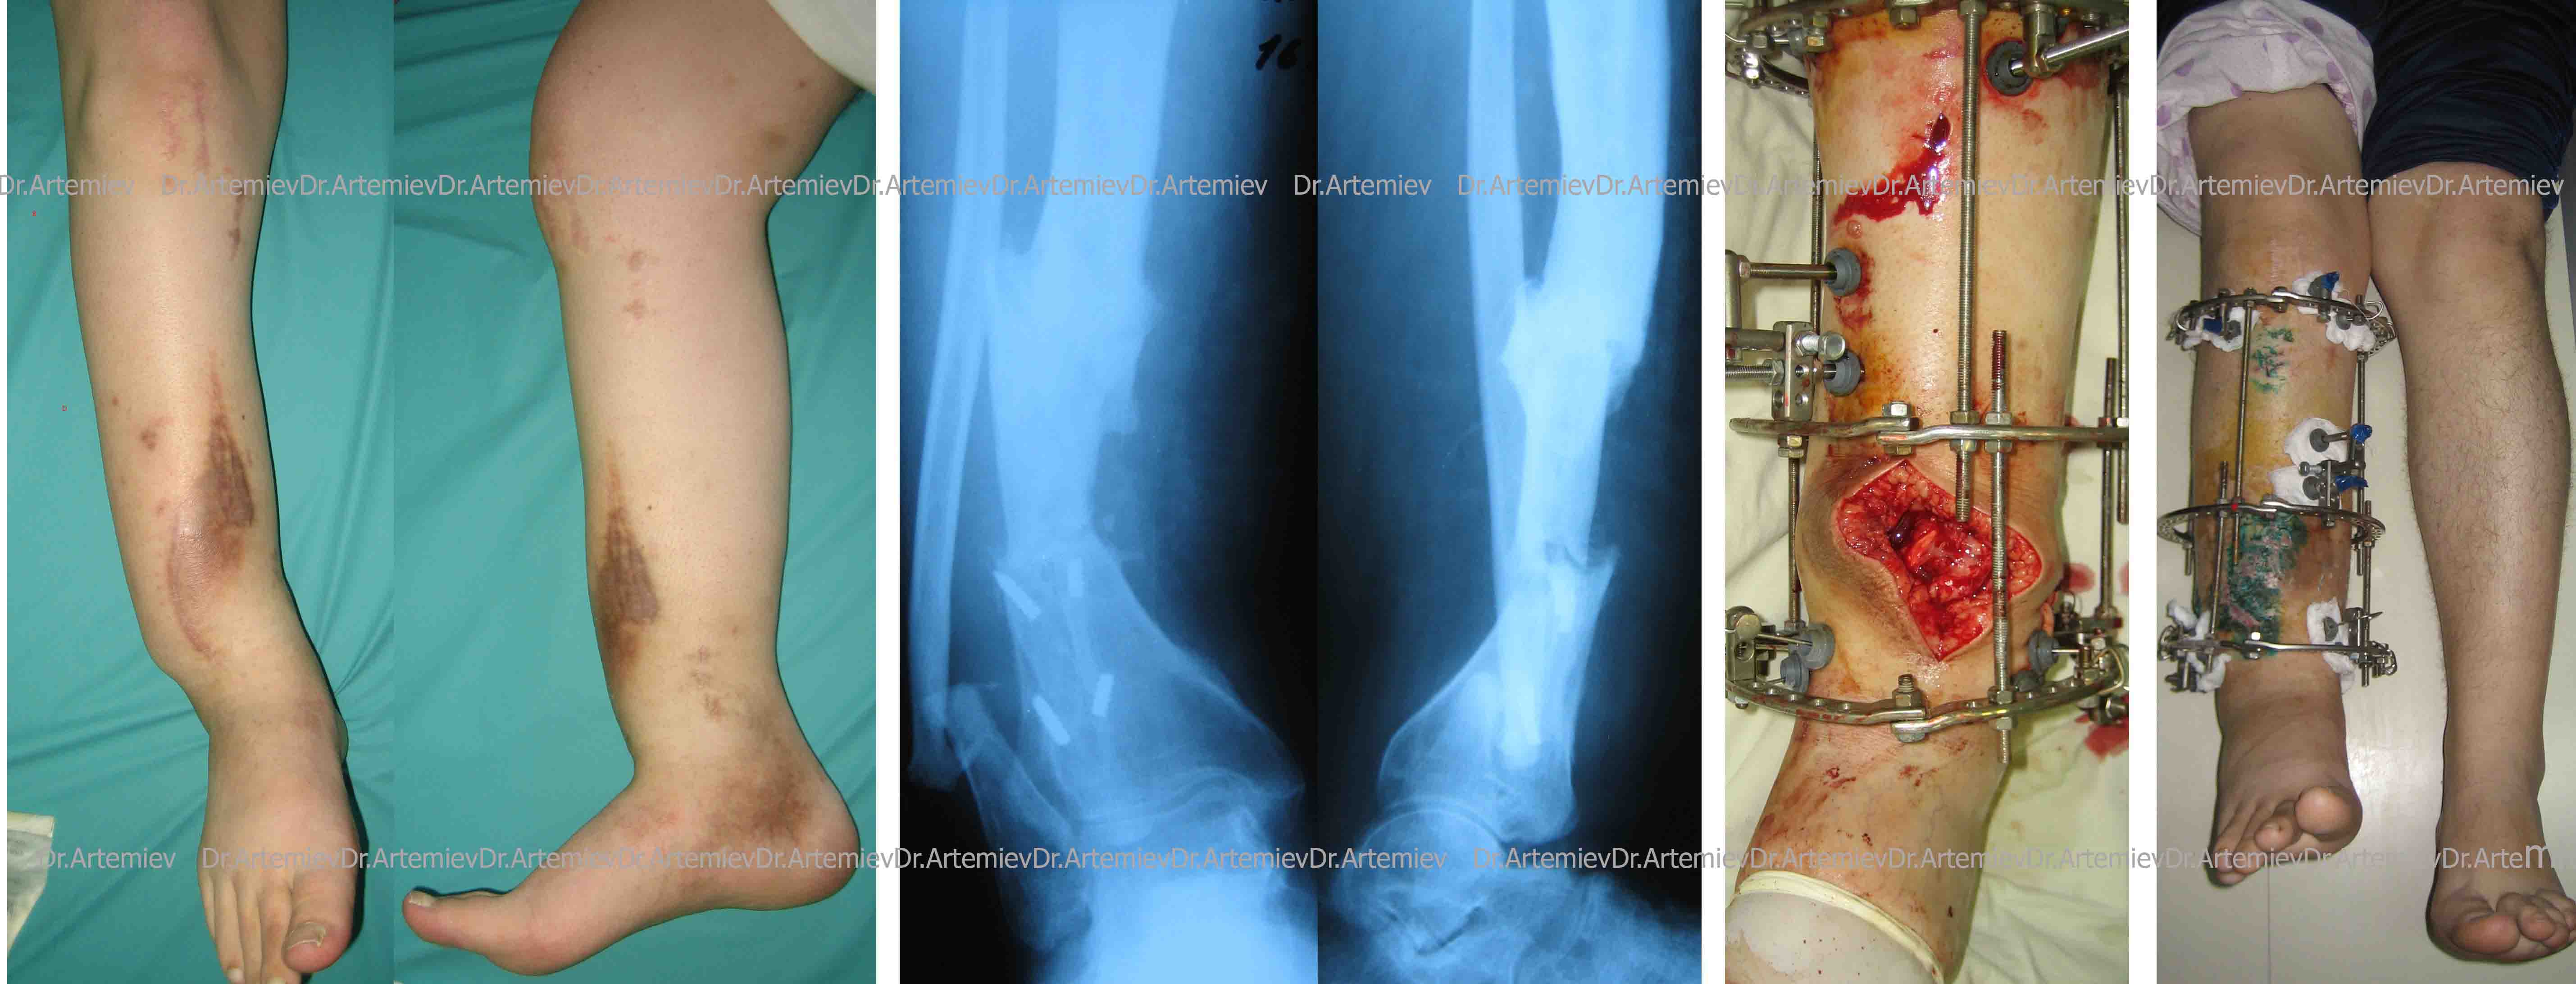

Месяца три назад наш коллега представлял одного больного с ложным суставом голени. Сложный анамнез - 10 лет лечения, 2 БИОСа (о чем говорят сломанные винты) и пр...

Я в итоге его прооперировал, сейчас он уже удлинил голень на величину имеющегося укорочения - 5 см.

Последние снимки будут на следующей неделе, а пока - то, что есть - во вложении.

>Госпитализирована женщина 52 года, 9 месяцев назад произведена КДО

>аппаратом Илизарова по поводу косого перелома  дистального метадиафиза

>костей левой голени,  образовался  тугой ложный сустав.

>В плане БИОС реконструктивным стержнем,  уважаемые коллеги какие будут

>мнение? ,